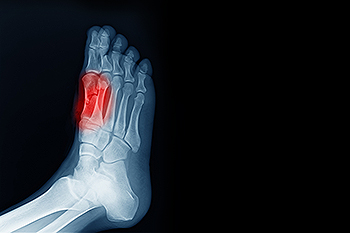

To conduct a diagnosis, the podiatrist will examine the ball of the foot and big toe. They will look for any outliers and check the movement of the toe. X-rays will be taken to rule out any other conditions and ensure that it is sesamoiditis.

Causes and Symptoms of a Sprained Toe

A sprained toe occurs when the ligaments in the toe are stretched or torn. This injury often results from trauma, such as stubbing the toe, or from hyperextension, where the joint is forced beyond its normal range of motion. A sprained toe is different from a broken toe, which involves damage to the bone rather than the ligament. Symptoms include pain, swelling, bruising, tenderness, and difficulty moving the toe. Some patients may also experience joint instability or hear a popping sound when the injury occurs. Any of the numerous joints in the toes can be affected, and the severity can range from minor ligament stretching to complete tears. Athletes and others who engage in activities involving sudden movements or uneven surfaces are at a higher risk of spraining a toe. A podiatrist can diagnose the injury by examining the toe, discussing its cause, and using imaging, such as X-rays, to rule out fractures. If you have injured your toe, it is suggested that you make an appointment with a podiatrist for a diagnosis and appropriate treatment.

Diagnosis

In many cases the cause of toe pain is obvious, but in others, a podiatrist may want to use more advanced methods to determine the problem. These can range from simple visual inspections and sensation tests to X-rays and MRI scans. Prior medical history, family medical history, and any recent physical traumatic events will all be taken into consideration for a proper diagnosis.